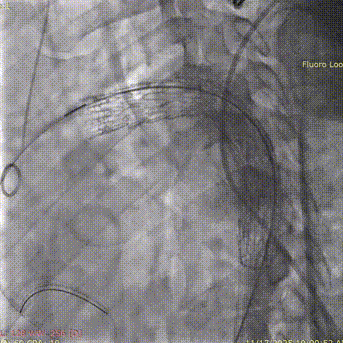

1. 患者全身麻醉后先进行弓上分支血管转流,该部分完成后,穿刺右侧股动脉及双侧肱动脉,置入金标猪尾导管进行主动脉弓部造影。

斑马导丝是治疗什么的「胸有乾坤」至简至易 行之有效—— Zone 0 TBE植入治疗弓部动脉瘤病例报道_https://www.jmylbn.com_新闻资讯_第13张

3. 右侧肱动脉置入斑马导丝,建立右肱动脉与股动脉之间工作轨道,沿加硬导丝及斑马导丝置入TBE主体支架(型号:TAC123715W)。调整机头角度,确认双导丝间无缠绕。

斑马导丝是治疗什么的「胸有乾坤」至简至易 行之有效—— Zone 0 TBE植入治疗弓部动脉瘤病例报道_https://www.jmylbn.com_新闻资讯_第16张

斑马导丝是治疗什么的「胸有乾坤」至简至易 行之有效—— Zone 0 TBE植入治疗弓部动脉瘤病例报道_https://www.jmylbn.com_新闻资讯_第17张

5. 右侧肱动脉长鞘造影确认支架位置。

斑马导丝是治疗什么的「胸有乾坤」至简至易 行之有效—— Zone 0 TBE植入治疗弓部动脉瘤病例报道_https://www.jmylbn.com_新闻资讯_第19张

6. 顶紧加硬导丝,让支架贴紧大弯侧,配合牵张导丝的牵拉力量,主体支架稳定释放。

斑马导丝是治疗什么的「胸有乾坤」至简至易 行之有效—— Zone 0 TBE植入治疗弓部动脉瘤病例报道_https://www.jmylbn.com_新闻资讯_第20张